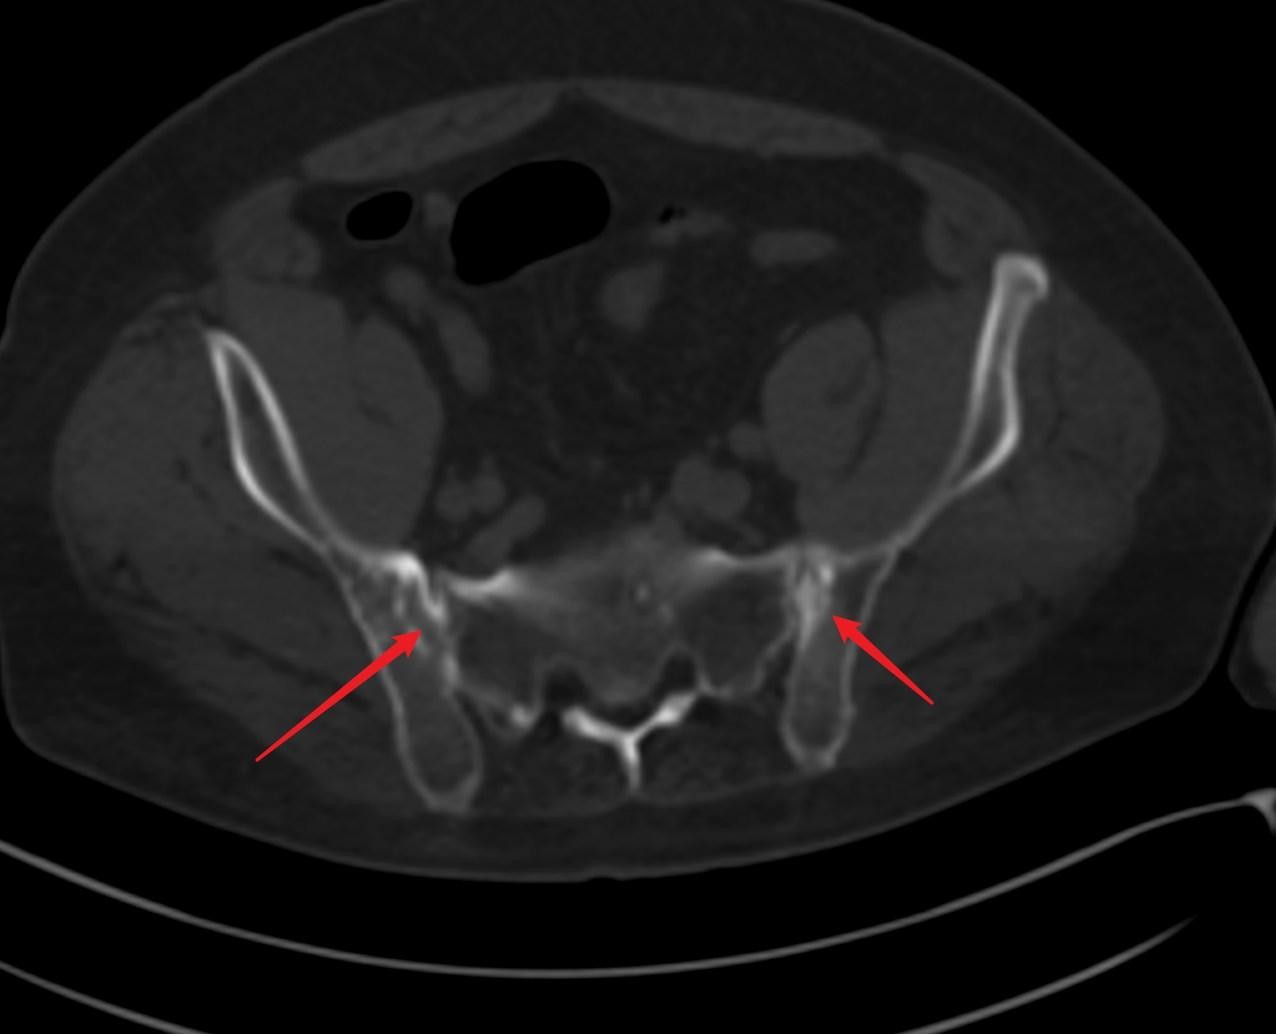

图3:较前一位患者严重↓

病变累多个椎体,脊柱呈竹节样改变,脊柱后凸更为明显。↓